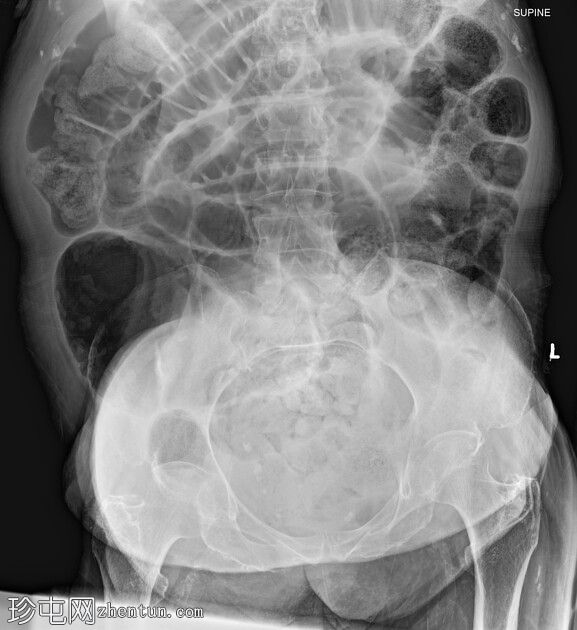

轴位增强扫描(门静脉期)

大肠内可见中度粪便。横结肠轻度扩张(约6.6厘米)。

数处小肠袢直径接近临界值(约3厘米),部分肠袢内可见粪便。

腹部中央及右侧可见数处小肠袢肠壁明显变薄,并可见肠壁积气。

少量腹水。

主动脉及其内脏分支可见明显动脉粥样硬化。肠系膜上动脉(SMA)开口处中度至重度狭窄;但开口后显影良好。

目前未见明显的门静脉-肠系膜静脉积气。

无气腹。